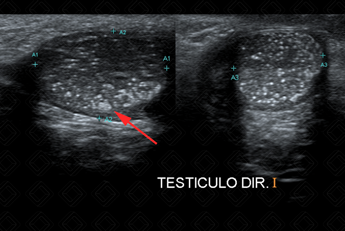

Texto alternativo para a imagem Figuras 1 e 2. Créditos: Dra. Elazir Mota - Rio de Janeiro/RJ

Descrição das figuras 1 e 2: Ultrassonografia de bolsa escrotal. Focos ecogênicos puntiformes, sem sombra acústica posterior, dispersos pelo parênquima testicular bilateralmente, compatível com microlitíase testicular (setas vermelhas).

Exame de imagem: O exame de escolha permanece sendo a ultrassonografia de bolsa escrotal. Na ultrassonografia, observamos focos hiperecoicos difusos pelo parênquima testicular, podendo apresentar ou não sombra acústica posterior. Na maioria dos casos, sua distribuição é bilateral e difusa pelo parênquima. No entanto, seu acometimento pode ser unilateral e focal (figuras acima).

Para ser considerada microlitíase testicular, devem existir cinco ou mais focos hiperecogênicos dispersos pelo parênquima testicular.